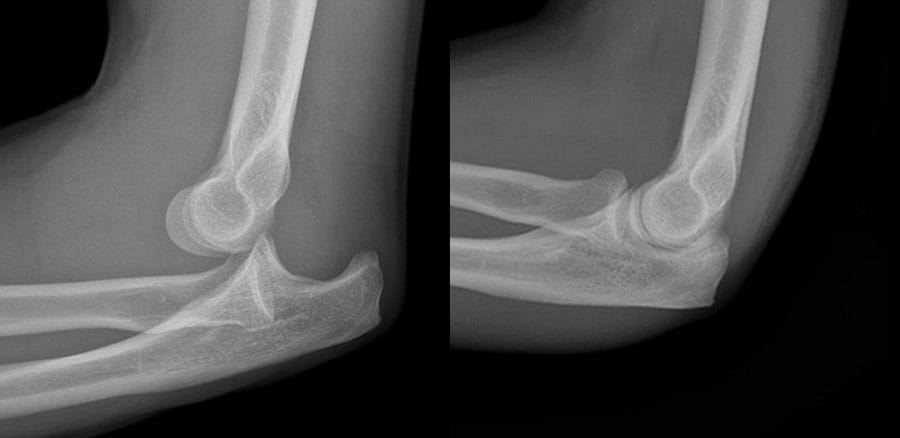

- Elbow

- Elbow.